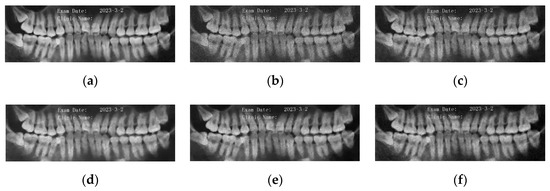

5.2. Numerical Simulations on Medical Images

5.2.2. Different Methods

- ADMM Method

5.2.3. Comparison with Other Variational Models